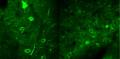

Plusieurs études rapportent la forte dépendance à la nicotine des patients schizophrènes. Les chercheurs de l'Institut Pasteur, du CNRS, de l'Inserm et de l'ENS sont parvenus à décrypter grâce à un modèle murin, le mode d'action de la nicotine sur les cellules du cortex préfrontal. Ils ont pu visualiser l'effet direct de la nicotine sur le rétablissement de l'activité normale des cellules nerveuses impliquées dans les troubles psychiatriques, comme la schizophrénie. Ces résultats sont parus dans Nature Medicine.